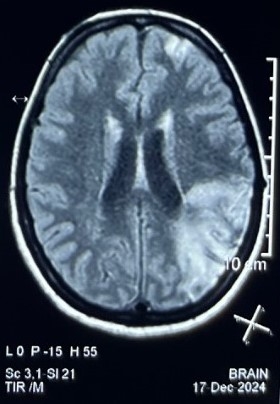

CEMRI BRAIN showed subacute infarct with hemorrhagic transformation in left parietal, temporal and occipital lobe, subacute infarct in left frontal lobe, foci of FFE in blooming in anterior limb of right and posterior limb of left internal capsule.CT angiography revealed diffuse mural thickening in the aortic arch,ascending and descending aorta, marked narrowing in the brachiocephalic artery and both common carotids, with saccular aneurysms, attenuation of intracranial ICA, ACA, and MCA, particularly on the right side.